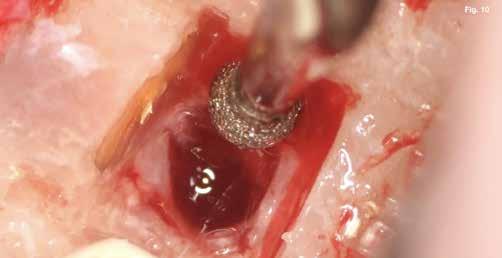

A szubmarginális teljes vastagságú lebenyt két felszabadító bemetszéssel végeztük egy 69-es számú, dupla lekerekített mikropengével (Swann–Morton) (6–7. ábra) A vestibularis csont ép volt, ezért csontablak-technikát alkalmaztunk és végeztünk (6–8. ábra) piezo készülékkel (Woodpecker DTE AI Surgery) és „US1, UC1” (Guilin Woodpecker Medical Instrument Co., LTD) hegyekkel. A blokkot az intraoperatív szakaszok alatt sóoldatban tartot-

tuk. Az apikális reszekciót (8. ábra) az „UC1” (Guilin Woodpecker Medical Instrument Co., LTD) segítségével végeztük el, és a gyökeret egy 3 mm-es „MM4” (Hu-Friedy Manufacturing Co. LLC) kerek tükörrel vizsgáltuk a VRF szempontjából (13. ábra). A gyökérvég polírozását (11. ábra) az „UL4” (Guilin Woodpecker Medical Instrument Co., LTD) segítségével végeztük. A csontos kripta küretizálása kézi küretezéssel történt, de a csontos kriptában lévő további hámbélés eltávolításával a gyógyulási folyamat felgyorsítása érdekében piezo „UL3” (Guilin Woodpecker Medical Instrument Co., LTD) piezo hegyet is használtunk (9–10. ábra). A három mm-es retropreparációt (14–17. ábra) a „JT2SA” hegy (B&L Biotech) segítségével végeztük el. A retropreparációt ismét ellenőriztük a guttapercha maradványok tekintetében, leöblítettük és papírhegyekkel meg-